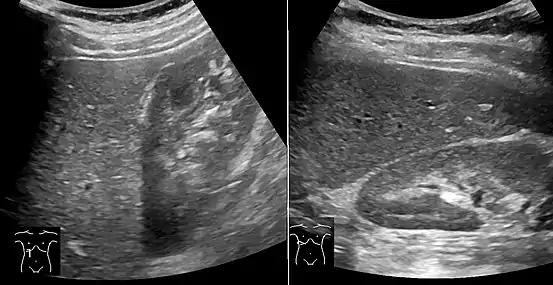

Medical imaging

Liver steatosis (fatty liver disease) as seen on CT

On X-ray computed tomography (CT), the increased fat component will decrease the density of the liver tissue, making the image less bright. Typically the density of the spleen and liver are roughly equivalent. In steatosis, there is a difference between the density and brightness of the two organs, with the liver appearing darker.[11] On ultrasound, fat is more echogenic (capable of reflecting sound waves). The combination of liver steatosis being dark on CT and bright on ultrasound is sometimes known as the flip flop sign.

On abdominal ultrasonography, steatosis is seen as a hyperechoic liver as compared to the normal kidney.